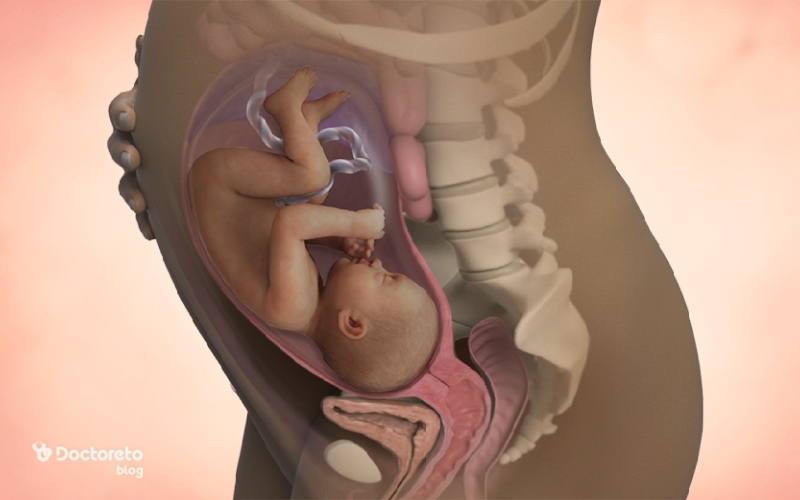

عکس جنین در هفته 32 بارداری

عکس جنین در هفته 32 بارداری جنین را در حالت خمیده نشان میدهد، با سر به سمت پایین و دست و پا نزدیک بدن. در این حالت، شکل کلی بدن، سر، دستها و پاها واضح و قابل تشخیص است و حرکات کششی و لگدهای او بهصورت سادهسازیشده دیده میشود. همچنین، جنین سی و دو هفته در این تصاویر تقریباً اندازه نهایی خود را یافته و حالت جمعشده داخل رحم را نشان میدهد.